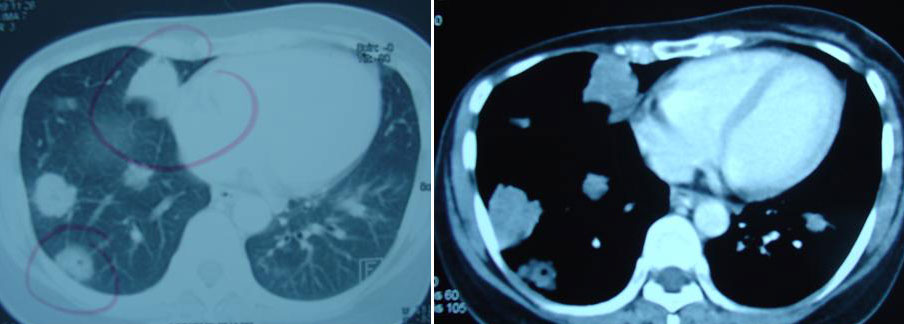

On 17 December 2008, York suffered headaches and was unable to sleep. A CT scan done on 19 December 2008, indicated multiple brain metastases.

Yee and her husband came to seek our help on 5 December 2008. Yee’s condition was serious. Her right arm was numb. She had no appetite. She was severely breathless. Even the supply of oxygen to her nostrils did not help at all. She told her husband she would rather die. In early February 2009, Yee was admitted to the hospital where the doctor suggested that she receive radiation to her brain. It was not to be – she died even before the treatment.